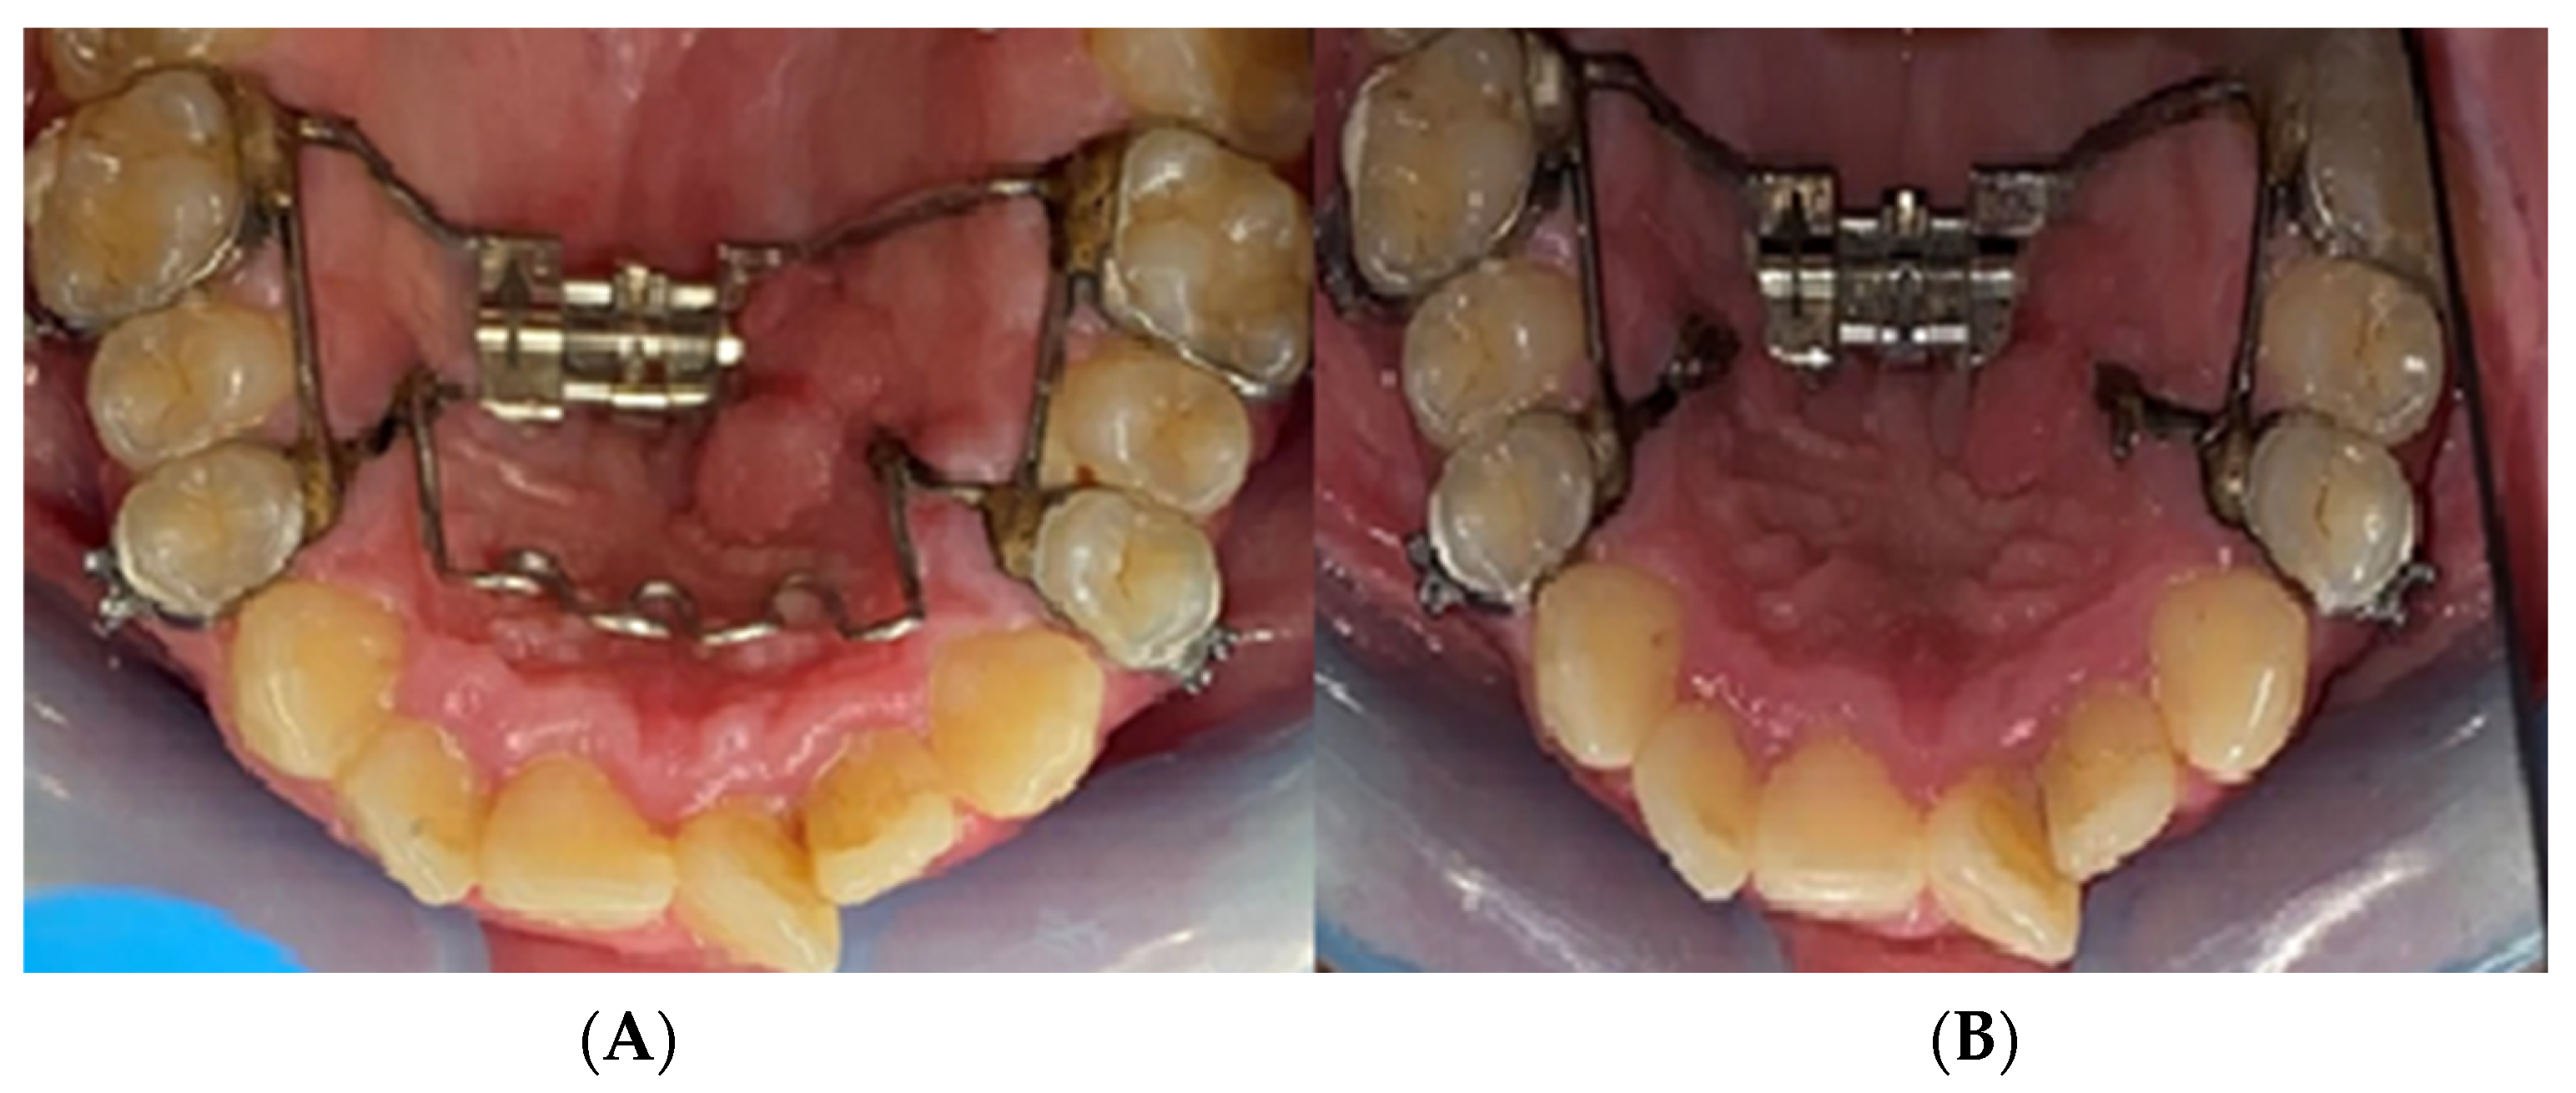

2.2. Palatal Expander Placement

2.3. Assessment of the Study Group

3. Results